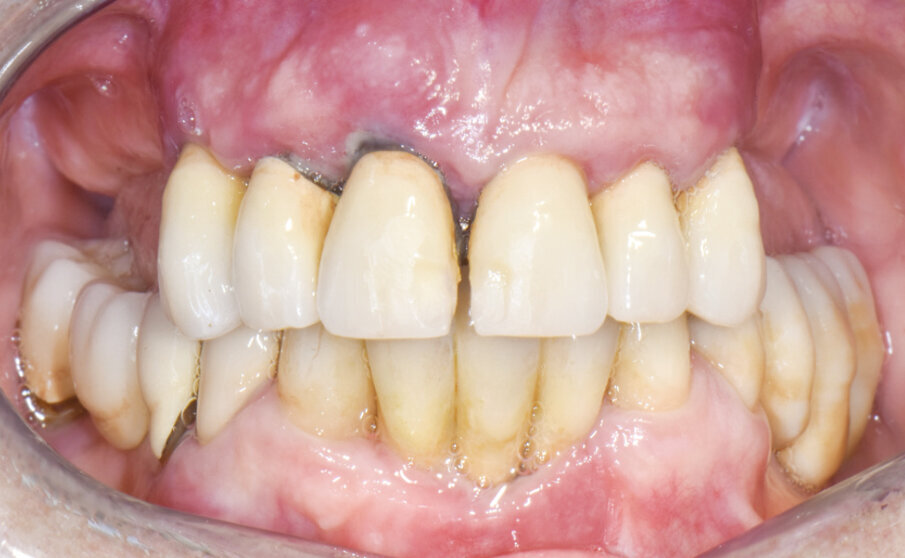

La paziente di sesso femminile di 63 anni si è rivolta a noi per riabilitare l’arcata superiore con una soluzione protesica fissa. Durante la prima visita si eseguono delle foto iniziali (Fig. 1), RX OPT, TAC CBCT e le prime impronte sia dell’arcata da trattare che dell’arcata antagonista. La registrazione del rapporto occlusale viene effettuata con Stone Byte. Dopo una prima analisi della situazione clinica e radiografica si illustrano alla paziente le opzioni possibili e si decide, di comune accordo, per una protesi avvitata tipo Toronto a carico immediato.